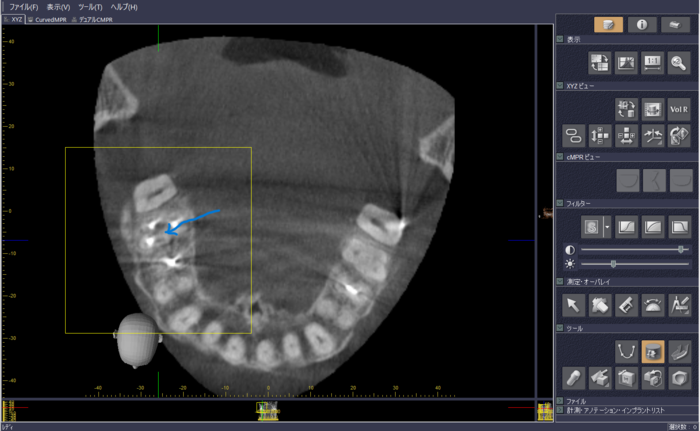

図4では、矢印で示している部分がくさび状に黒く透けて見えます。これは、歯を支えている顎の骨(歯槽骨)が歯周病で溶けているのを示す画像です。これは、通常のレントゲンでも2次元的に見ることはできるのですが、CTだといろんな角度から見ることが出来るので、3次元的に歯周病がどの程度進んでいるかの診断に役立ちます。